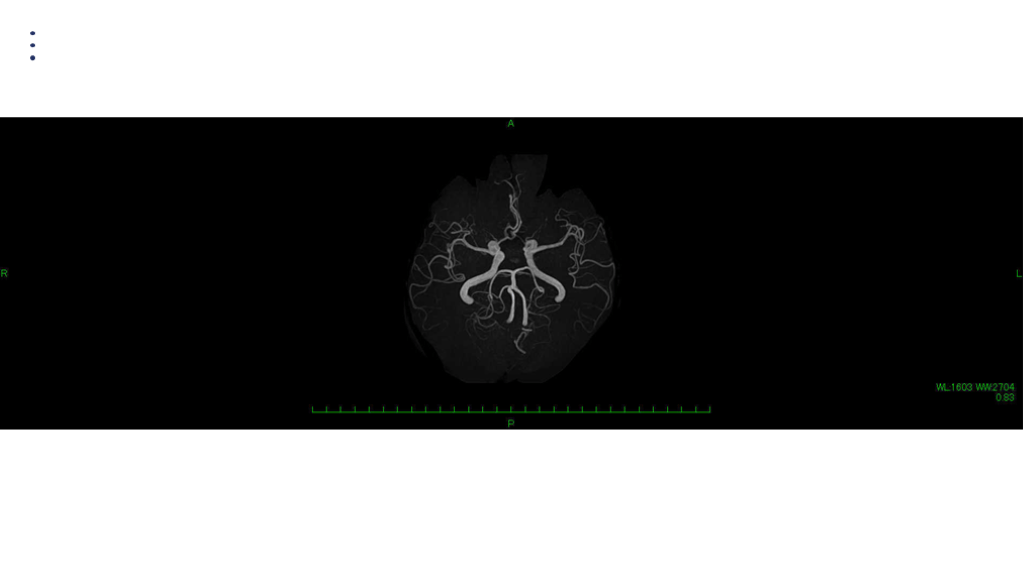

画像 所見 DAY 14 MRA 悪化

50歳 男性 外来経過: 一日に1-2回頭痛発作を認めた。 入浴によって誘発された。 排便によって必ず誘発された。排便に対する恐怖の訴えあり。 その後頭痛頻度は減っていった。 DAY 14に一過性の右片麻痺があり、ER受診。MRI再検した。